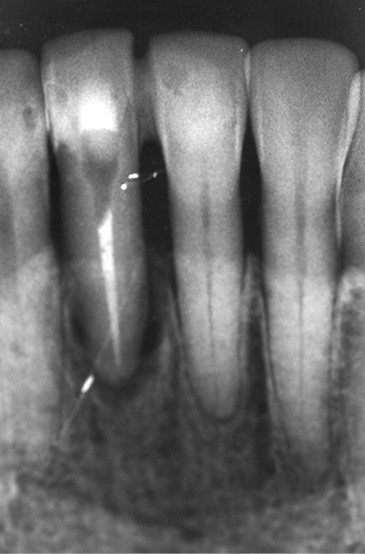

Le cas clinique présenté dans cet article traite de la gestion d’un édentement mandibulaire dans le secteur antérieur, survenu après un accident de la voie publique ayant entraîné une aggravation d’une lésion parodontale existante (fig. 1). Cette pathologie a nécessité l’extraction de la dent qui avait été traitée huit ans auparavant par une attelle-bridge en zircone, compte tenu de l’impossibilité médicale de mettre en place un implant (fig. 2).

À l‘époque de la réalisation de l’attelle, le choix du matériau se faisait entre le métal et la zircone. Les inconvénients majeurs de ces deux matériaux résident dans la complexité du protocole de collage [3] d’une part, et dans le manque de fiabilité à long terme de ce dernier, d’autre part (fig. 4).